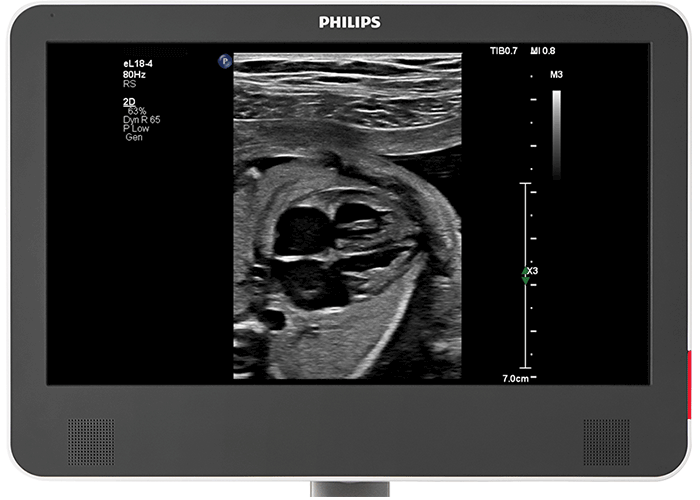

胎児検査用の優れたイメージング eL18-4 PureWave リニアトランスジューサは、妊娠初期および妊娠中期の胎児エコー検査において、優れた 2D 解像度とペネトレーションを提供します。さらに、X6-1 xMATRIX トランスジューサは、高画質な 2 D画像と胎児心臓の Live 3D 画像を提供します。

小さな患者のための 2D TEE フィリップスのマルチプレーン MicroTEE S8-3t は細径シャフトを実現しており、重要な心臓カテーテル術や外科手術中における 2.5kg 程度の極めて小さな乳児のイメージング、および新生児の高性能リアルタイムイメージングが可能です。